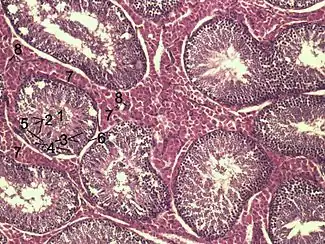

![]() Histological section through testicular parenchyma of a boar. 1 Lumen of Tubulus seminiferus contortus, 2 spermatids, 3 spermatocytes, 4 spermatogonia, 5 Sertoli cell, 6 Myofibroblasts, 7 Leydig cells, 8 capillaries | |